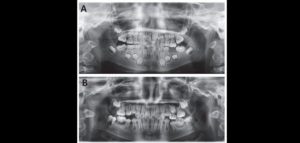

158 – Uso intraoperatorio de la CBCT para la identificación y localización de canales calcificados

Se sabe que la tomografía computarizada de haz cónico (CBCT) produce exploraciones tridimensionales de la dentición, las estructuras duras maxilofaciales y la relación de las